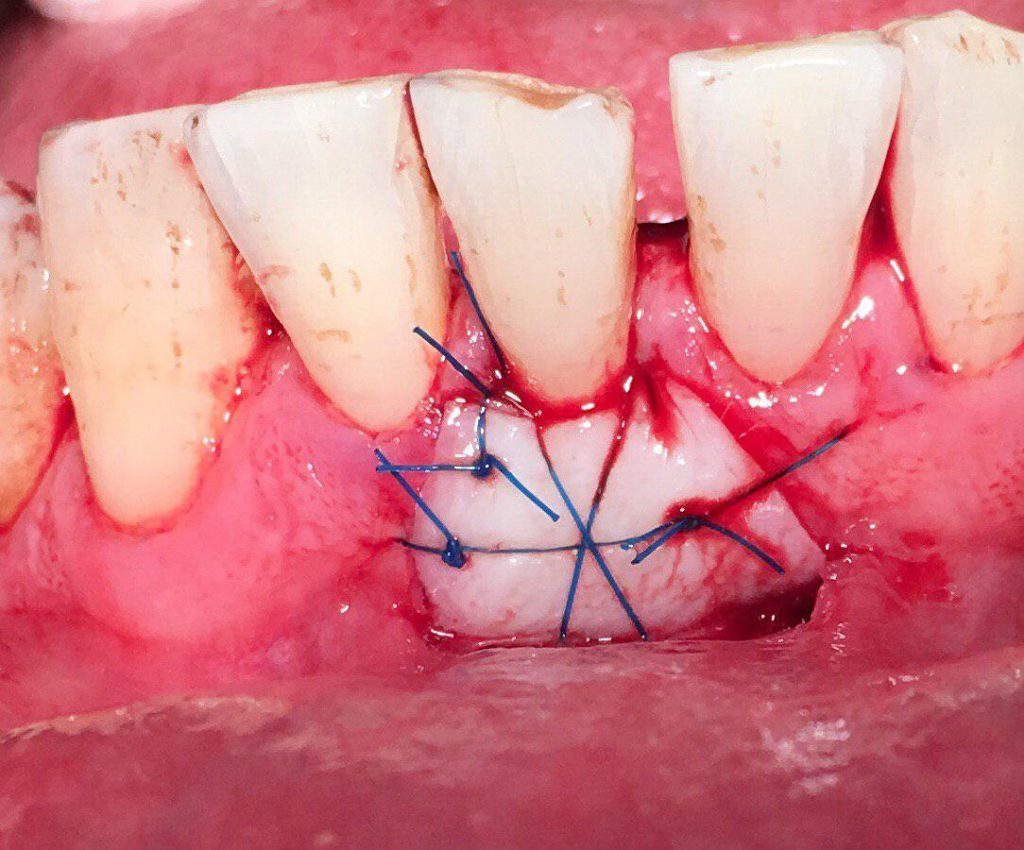

جراحی پیوند لثه جهت افزایش لثه چسبنده و پوشش ریشه و بهبود تحلیل لثه

جراحی پیوند استخوان جهت افزایش میزان استخوان و آماده سازی برای گذاشتن ایمپنت